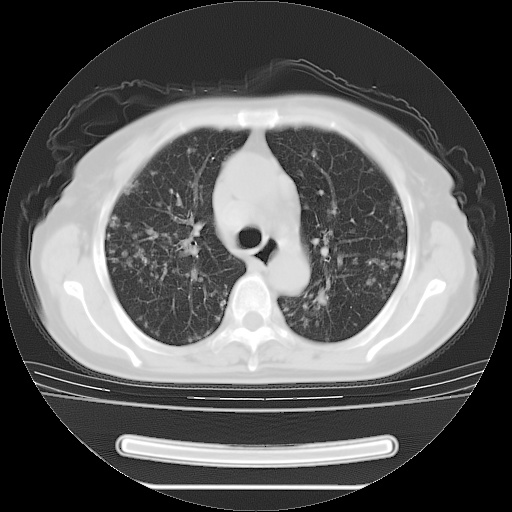

ct示两肺粟粒状病灶,以两肺上叶尖后段及下叶背段分布为主;首先考虑结核。请战友们分析。

考虑 1 弥漫性泛细支气管炎, 2 结核不除外/.  有小叶中心结节 和 树芽征!!

两肺内病灶呈小结节状和树芽状,纵膈的肿大的淋巴结密度不均匀,并见有钙化,考虑为两肺结核可能更大些。

两肺内病灶呈小结节状和树芽状,纵膈的肿大的淋巴结密度不均匀,并见有钙化,多形态病灶,考虑为两肺结核,肝内考虑小囊肿。

病灶以结节为主,大部分边界清楚,分布不均,病灶形态较单一,偶见空泡征,纵膈淋巴结肿大钙化,无结核中毒症状考虑 感染性病变【真菌类可能性大】,细支气管肺泡癌。其他待排

两肺内病灶呈小结节状和树芽状,纵膈的肿大的淋巴结密度不均匀,并见有钙化,结合(曾抗炎治疗无效果,最近抗结核治疗约半月余,症状缓解。)

考虑为两肺结核可能更大些。

纵隔见肿大淋巴结并钙化,首先考虑结核,但感觉小结节像“挂果”征,分布位于支气管边缘,所以不排外肺泡癌,建议抗唠后复查吧?不然是癌的话,也不好治吧?化疗?